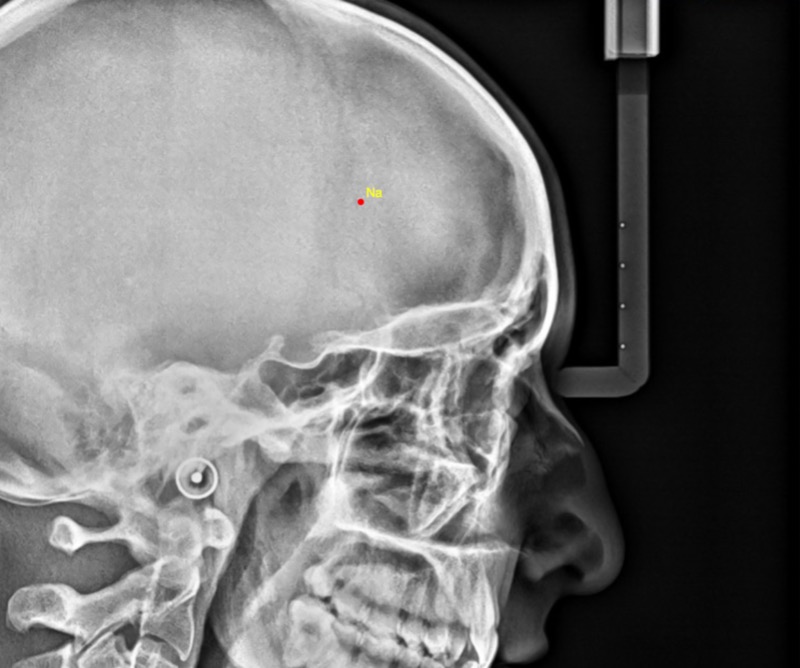

Dear Webceph technical support,

I have tried using the "manual digitalization" function. However, when I input the points, they are positioned in a completely different location from the one I selected (as can be seen from the attached image). I am using macOS with Safari.